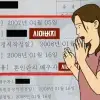

미국 의사 샘 갈리가 올린 한 남성의 엑스레인 사진. 엑스(X·옛 트위터) 캡처

24일(현지시간) 영국 일간 데일리메일, 더선 등의 보도에 따르면 미국 응급실 의사 샘 갈리는 지난 20일 한 남성의 엑스레이 사진을 엑스(X·옛 트위터)에 올리며 “내가 본 가장 이상한 엑스레이 사진”이라고 적었다.

그가 공개한 익명의 남성 엑스레이 사진에는 엉덩이와 다리 부분에 길쭉한 모양의 쌀알같이 생긴 것들이 퍼져 있다.

갈리는 해당 남성의 질환에 관해 “돼지 유구조충 유충에 의한 낭미충증”이라고 설명했다. 이 남성은 엑스레이 사진을 찍으러 병원에 찾았다가 질환에 걸렸다는 사실을 알게 됐다. 남성은 생명에는 지장이 없는 것으로 알려졌다.